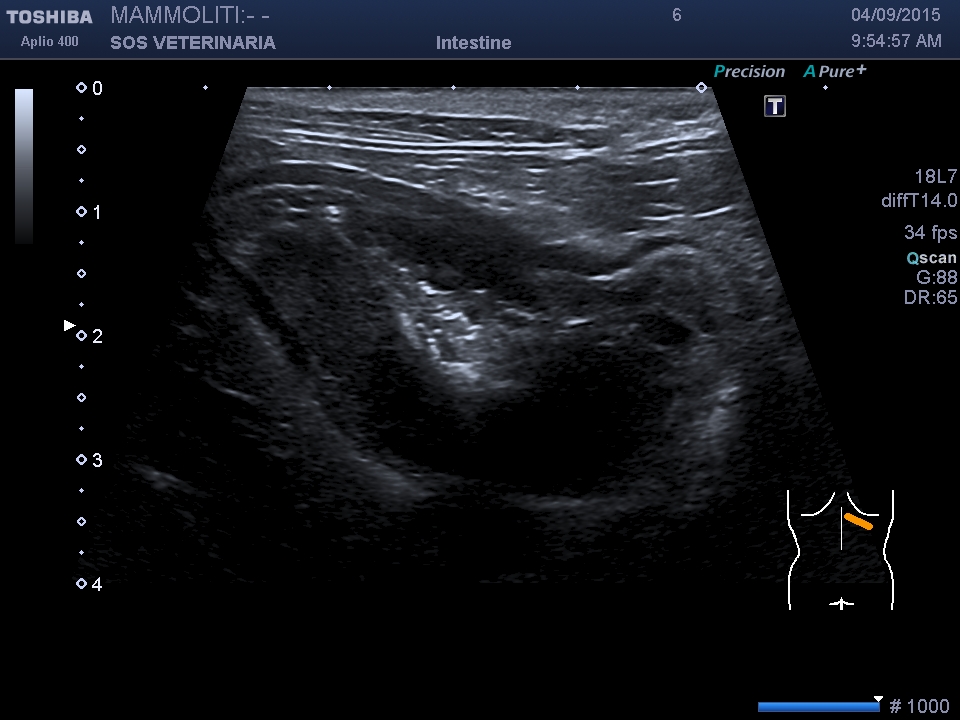

linfoma gastrico

gatta, comune europea,7 anni , emesi ricorrente da diversi mesi ,analisi del sangue nulla di significativo ,alla palpazione profonda dell’addome si avvisava sensazione di duro a livello gastrico ,l’esamo ecografico normalmente poco scarsamente sensibile e specifico per le patologie gastriche ,in questo caso, molto avanzato, ha evidenziato l’ispessimento della parete,  eseguita il giorno dopo la gastroscopia  ha confermato purtroppo la diagnosi ,

sezione sagittale